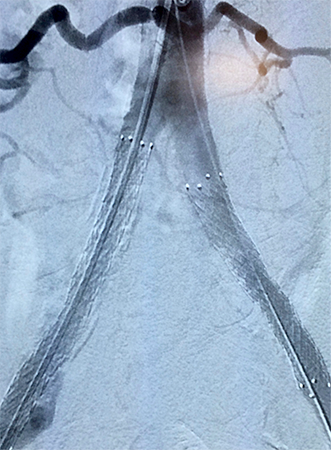

Tratamento de Aneurismas de Aorta, Periféricos ou Vicerais

É o tratamento de artérias dilatadas por métodos endovasculares pouco invasivos. O procedimento pode alterar de acordo com a região localizada, do tamanho e da condição do aneurisma. Atualmente a cirurgia vascular dispõe em seu arsenal para o tratamento de aneurismas, um método seguro e menos invasivo que a cirurgia convencional. O tratamento endovascular para aneurismas de aorta, viscerais e periféricos possibilita uma melhora na qualidade de vida dos pacientes de uma forma menos agressiva, objetivando evitar as principais complicações dessas doenças. São utilizados dispositivos de implante totalmente percutâneo e o procedimento é realizado em local específico para estes casos. Após detalhada análise de exames complementares: ultrassom, angiotomografia, angiorressonância, o cirurgião vascular opta pela melhor alternativa de tratamento baseado na anatomia da doença e no perfil de cada paciente.